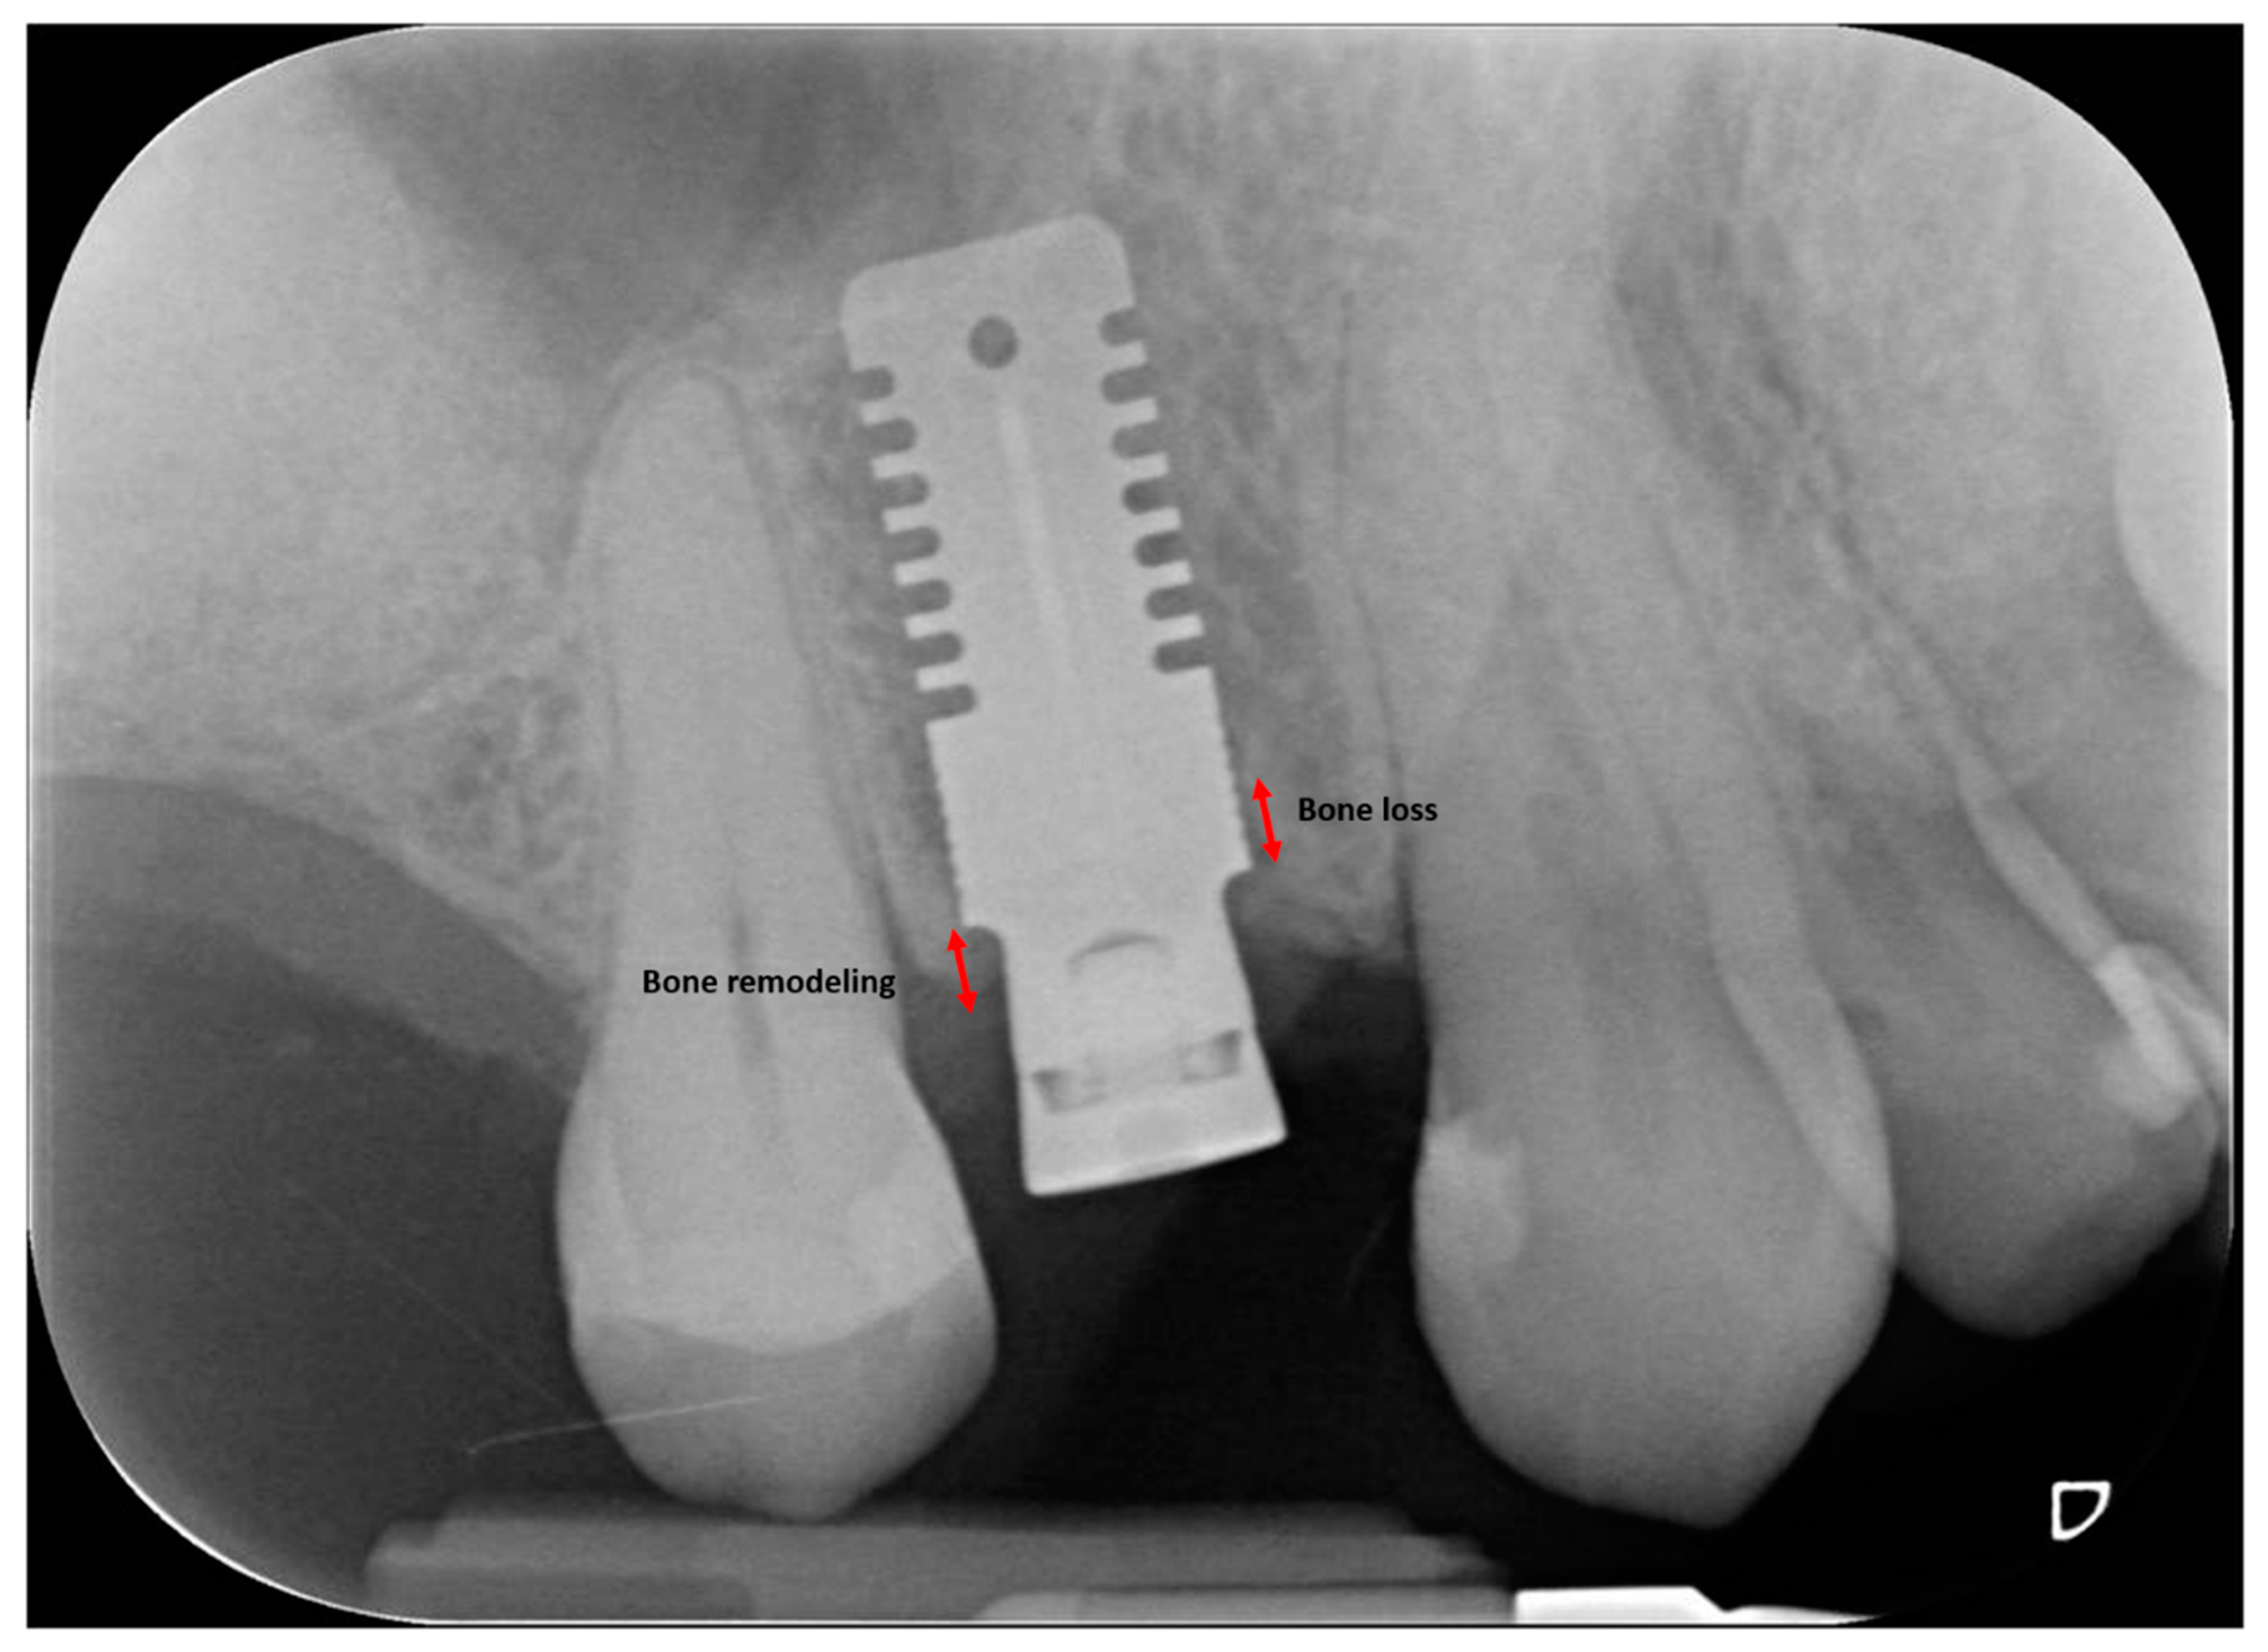

2.3. Radiographic Measurements

| MBL T1-T0 | 0.38 ± 0.46 | <0.001 * | 0.40 ± 0.58 | <0.001 * | 0.38 ± 0.48 | <0.001 * |

| MBL T2-T0 | 0.43 ± 0.57 | <0.001 * | 0.60 ± 0.74 | <0.001 * | 0.60 ± 0.52 | <0.001 * |

| MBL T2-T1 | 0.09 ± 0.22 | <0.001 * | 0.20 ± 0.36 | <0.001 * | 0.20 ± 0.19 | <0.001 * |